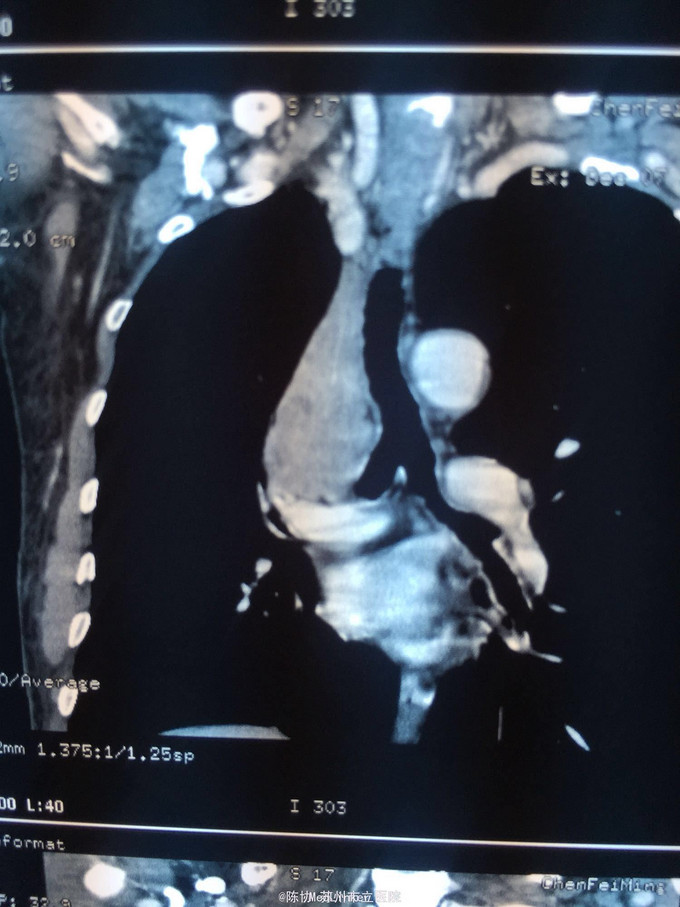

主诉:体检发现右上肺不张半月 77岁男,半月前体检发现右上肺不张,无不适。无消瘦,无咳血,无干咳。去年4月右上肺炎,抗生素治愈,当时CT未见肺肿块。入院支气管镜发现右上支气管开口组织增厚闭塞,开口近侧有隆起约3x3平方毫米,取活检5块病理示中度非典型增生。CT提示在右侧主支气管外侧有30x30平方毫米块影,压迫右上支气管开口处。三大常规和生化检查正常,肿瘤指标正常,TAP正常。

右侧中央型肺癌 重做支气管镜,精于定位找到病症组织,获得病理诊断来指导治疗。 胸外科医生不建议手术,理由是肿瘤位置靠近主支气管和气管,袖状切除不一定看干净。 请问正确的诊断,和比较合理的治疗方法是什么?求助大家思考评论